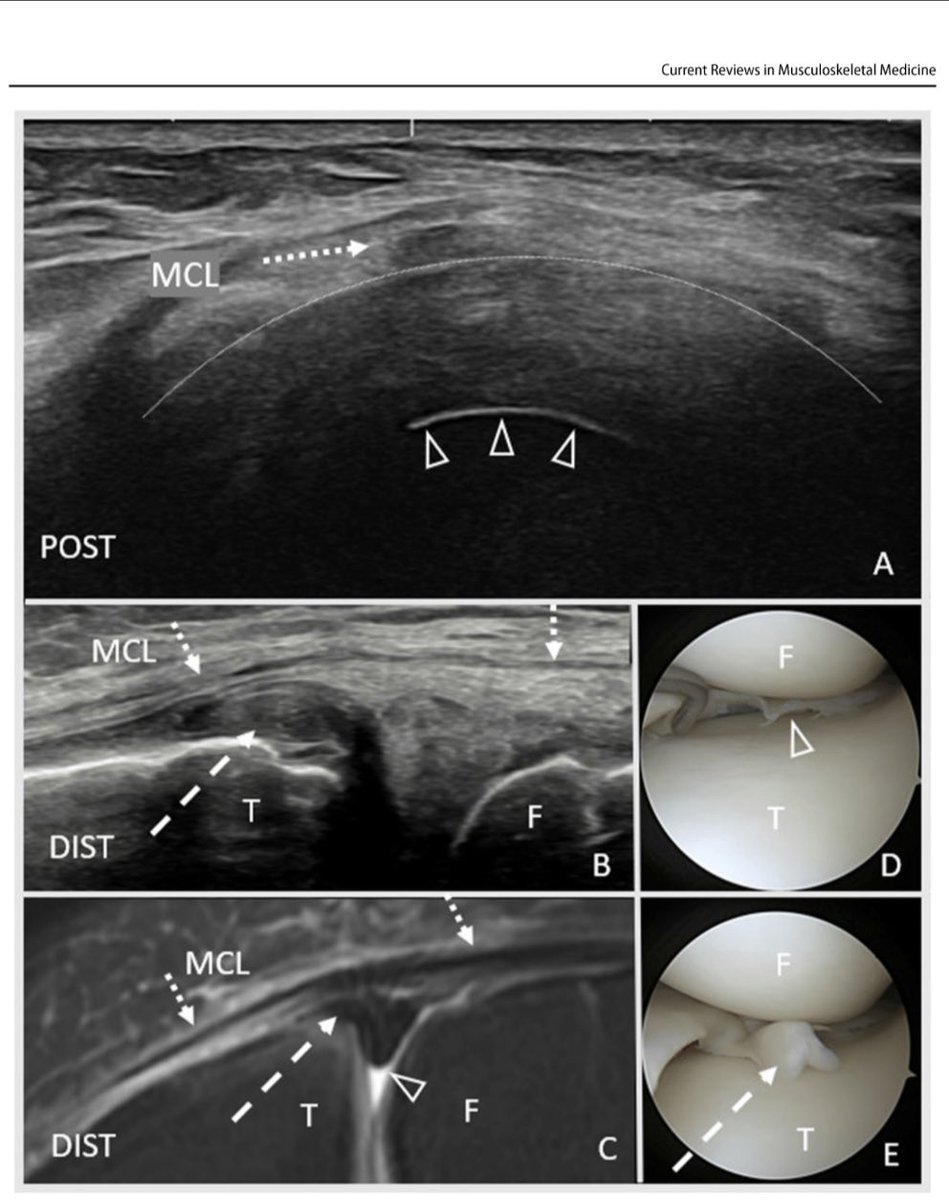

Know about #meniscus ultrasound? If not, read my latest #research on evaluation and treatment of meniscal disorders with #ultrasound , published with Springer Nature at rdcu.be/dfFjK Mayo Clinic Orthopedics and Sports Medicine Shelby Johnson, MD